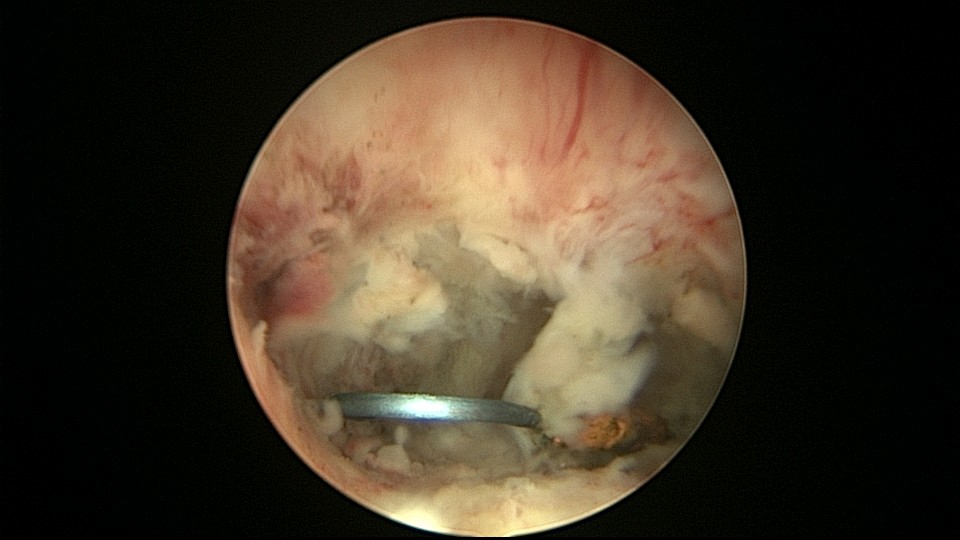

患者48岁,G3P1,顺产1次。安环10年,绝经1年,外院取环失败,子宫穿孔,腹部平片无异常。宫腔镜见宫腔广泛致密粘连,V型环与粘连组织嵌顿,取环钩盲视下多次尝试钩取节育环,均失败。取环钩循镜鞘外侧进入宫腔,直视下钩住节育环,顺利取出。再次置镜寻找子宫穿孔处并进入盆腔,见网膜脂肪组织,确认无活动性出血及盆腔积血,结束手术。